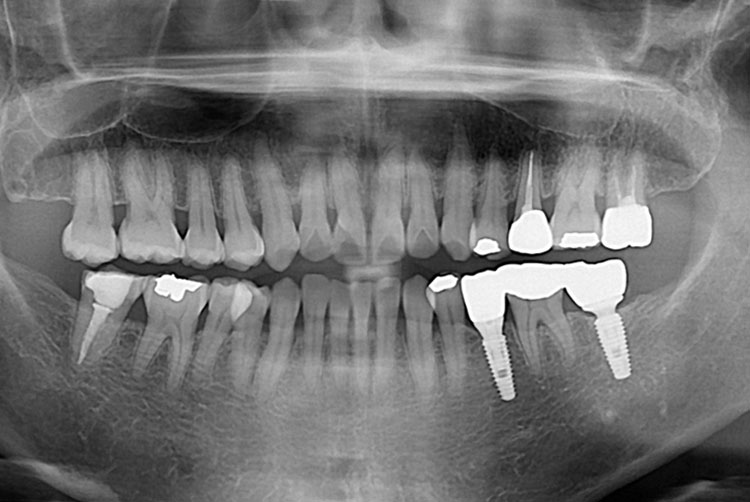

치료후 : 2019-11-29

세종치과는 많은 환자와 다양한 케이스를 바탕으로 항상 편안한 임플란트 수술을 제공하고자 노력하고,

오래동안 튼튼히 쓸 수 있는 임플란트 수술을 가장 큰 목표로 삼고 있습니다.